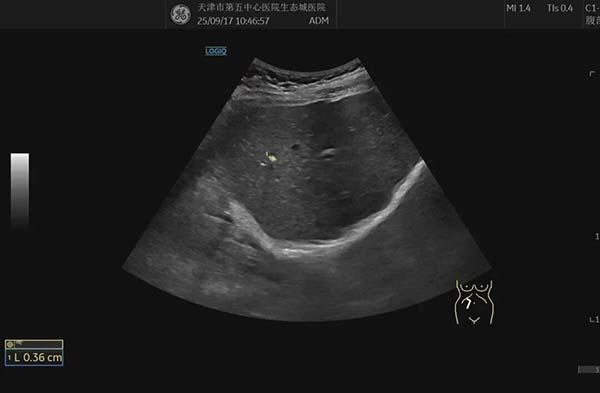

简单来说,肝内钙化灶就是肝脏某些部位出现了微小的钙盐沉积。在超声图像上,它们看起来像一个个亮白色的小点或小斑块。

它不是肿瘤,也不是活动性肝病,更像是肝脏过去某次轻微损伤后,在愈合过程中留下的一道“小疤痕”。就像皮肤受伤结痂脱落会留下印记一样,肝内钙化灶就是肝脏内部的“静态印记”,只是这个印记里含有钙质。